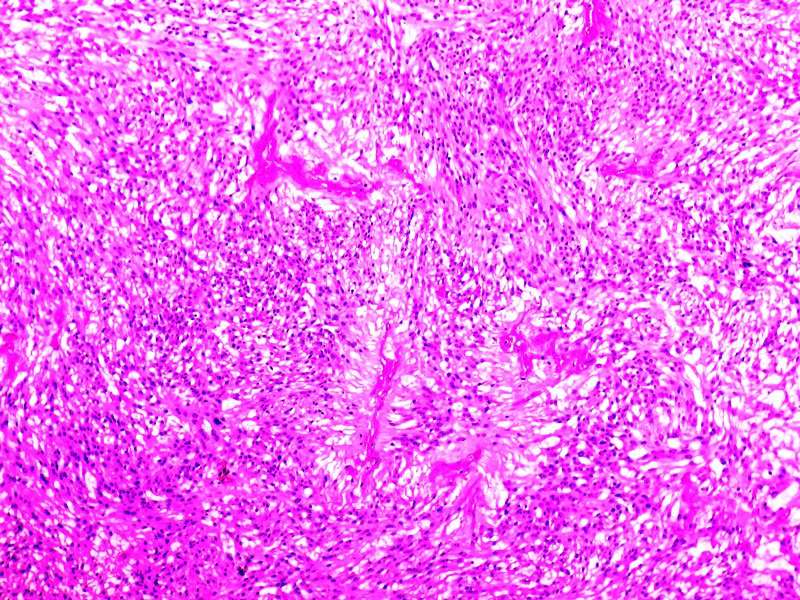

Elastofibroma de región escapular. Tinción HE